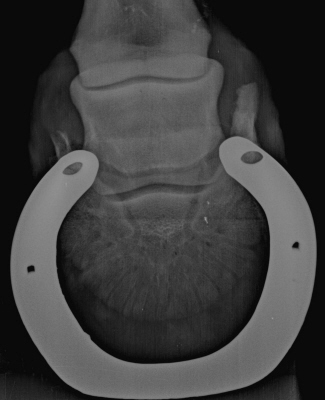

Oxspringaufnahme

Hufknorpelverknöcherung, Strahlbein nicht pathologisch verändert